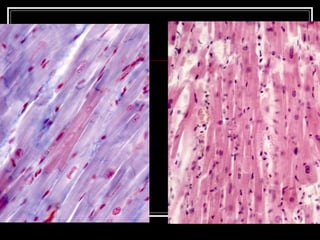

TEJIDO MUS. LISO CELULAS AHUSADAS- FUSO UN SOLO NUCLEO  SE ENCUENTRA VISCERAS INERVACION SNAUTONOMO ES INVOLUNTARIO UNIDAS POR TEJ. CONJUNTIVO

TEJIDO MUSCULAR LISO CONTRACCION LENTA , SOSTENIDA Y PARCAIL.  EL ESTADO DE CONTRACCIÓN PARCIAL PROLONGADA EN EL MÚSCULO ESTRIADO O LISO ES EL  TONO MUSCULAR CITOPLASMA :FILAMENTOS ACTINA, MIOSINA , INTERMEDIOS

TEJIDO MUSC. ESTRIADO CELULAS ALARGADAS MUCHOS NUCLEOS VOLUNTARIO FORMANDO MUSCULOS ESQUELETICOS INERVACION SNC

TEJ. MUS. ESTRIADO RODEADO POR TEJ. CONJUNTIVO EPIMISIO PERIMISIO ENDOMISIO

TEJ. MUS. ESTRIADORODEADO POR TEJ. CONJUNTIVO EPIMISIO PERIMISIO ENDOMISIO